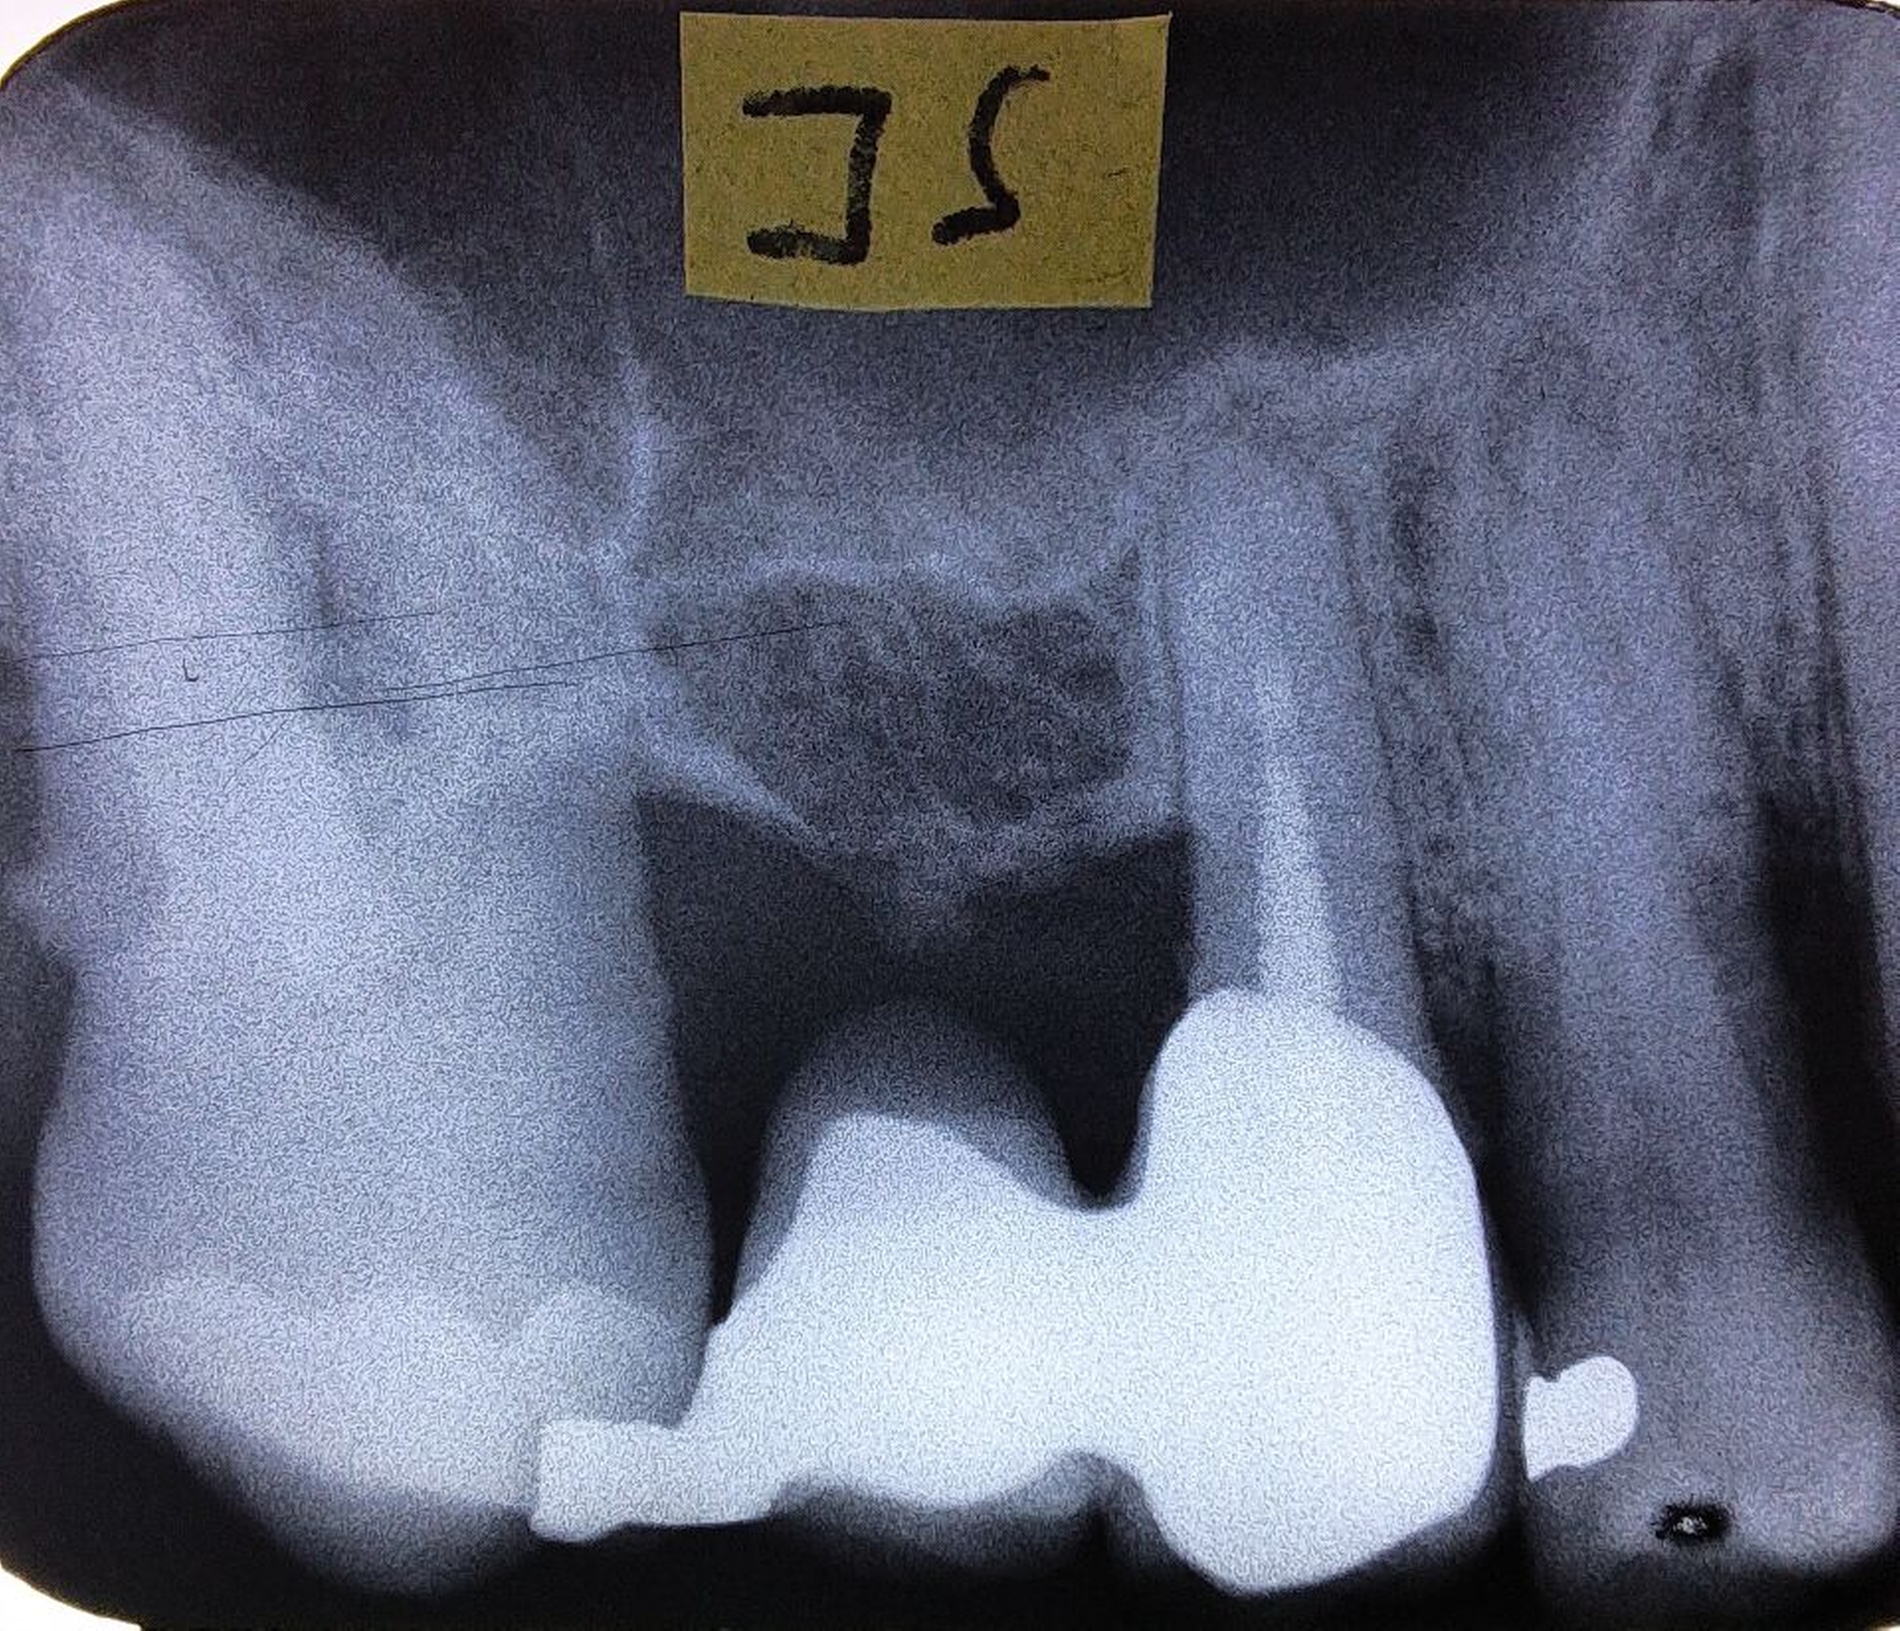

In den Abbildungen werden drei Fallbeispiele vorgestellt, bei denen alle Brücken noch in situ sind: